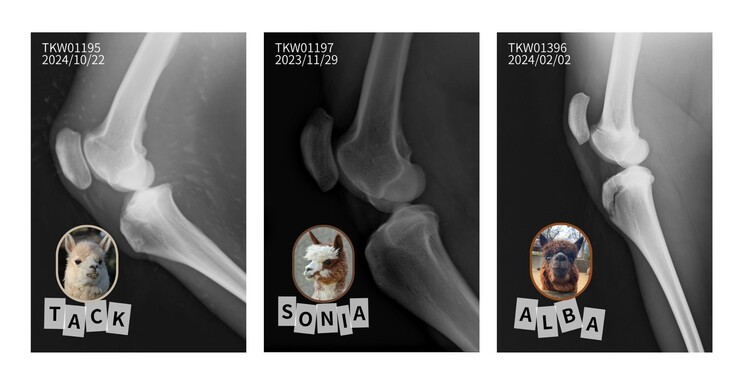

当園で暮らす3頭のアルパカ、タック・ソニア・アルバの膝蓋骨のレントゲン写真のポストカードです。

3頭の膝蓋骨をじっくりと見比べてみませんか?

●アルパカの膝蓋骨レントゲン写真ポストカード3枚(タック、ソニア、アルバ)